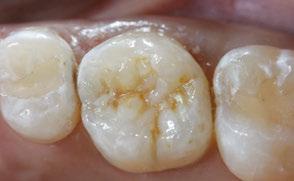

The 5-year-old patient featured in this case study did not benefit from early oral care and had multiple carious lesions. Considering the young age, high caries risk, and the uncertainty of compliance with follow-up appointments, I wanted to restore and seal all teeth in one visit. One quadrant is shown in this case study. The carious lesion on tooth J (65) was cavitated and prepared, restored, and sealed. Tooth I (64) was non-carious and would only be sealed (Figure 1).

surface of tooth I (64) was also lightly abraded with a diamond bur (Figure 2). The preparations were selectively etched with phosphoric acid, rinsed, and lightly dried (Figure 3). Bonding agent was applied to the entire occlusal surfaces of both teeth, air thinned, and light-cured (Figure 4).

Tooth J (65) was bulk-filled with Activa Kids. For this fast injection technique, I place the dispensing tip at the floor of the preparation and extrude the material without removing the tip until the preparation is completely filled (Figure 5). I like to do some minor manipulation of the filling material with hand instruments to create anatomy, as well as to ensure the material is flush with the surface of the preparation, and no air is trapped inside. Activa Kids is dual-cure, ideal for bulk filling, and can be cured with all lights. A thin topcoat of Activa Presto was placed as a sealant on the entire occlusal surface of teeth I and J (64 and 65) (Figure 6). Figure 7 shows the final clinical situation.

Figure 1 (left): Caries lesion on tooth J (65). Figure 2 (center): Preparation of tooth J (65) and abraded occlusal surface of tooth I (64). Figure 3 (right): Selective etch of enamel Figure 4 (left): Bonding agent is applied to both teeth I and J (64 and 65). Figure 5 (right): The preparation is filled with ACTIVA Kids Figure 6 (left): A thin topcoat of ACTIVA Presto is applied to the occlusal surfaces of teeth I and J (64, 65). Figure 7 (right): Final result